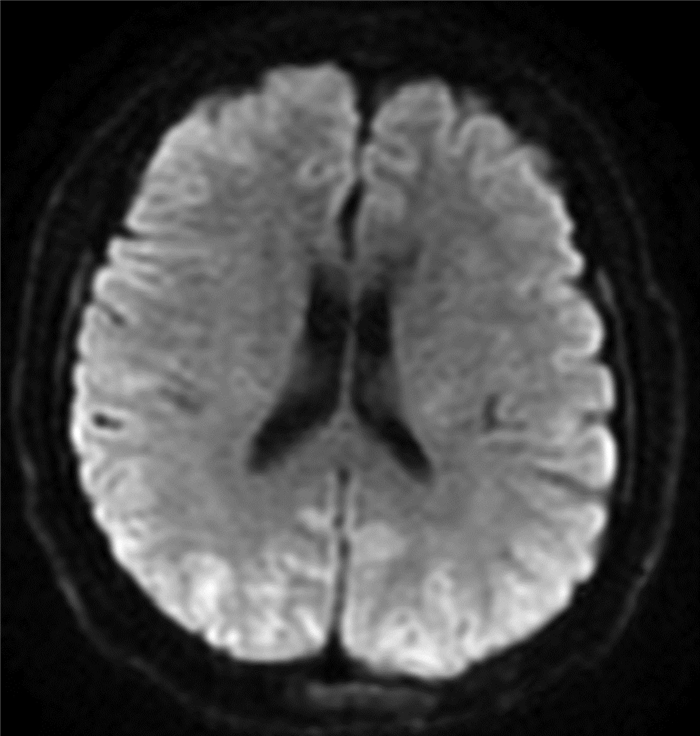

食管胃静脉曲张内镜下治疗后并发可逆性后部脑病综合征1例报告

于亭亭, 姜珊珊, 朱萌然, 白云

2022, 38(1): 177-179. DOI: 10.3969/j.issn.1001-5256.2022.01.030

摘要(816) HTML (198) PDF (3069KB)(57)

摘要: